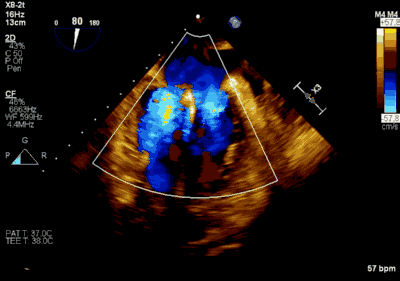

患者为66岁老年男性,4个月余前因“急性心肌梗死合并二尖瓣后叶腱索断裂”出现心源性休克,在IABP支持下仍反复发作左心心力衰竭,经过急诊血运重建联合优化药物治疗后症状好转,但术后多次发作严重左心心力衰竭,超声心动图评估二尖瓣反流急性增加至极重度,左房、左室显著扩大。此次主诉“反复胸闷、气促4月余”入院。诊断:心脏瓣膜病 二尖瓣脱垂伴重度关闭不全 二尖瓣后叶腱索断裂 心功能IV级(NYHA分级) 。术前经胸超声心动图示:全心扩大,二尖瓣后叶脱垂、腱索断裂合并重度关闭不全(DMR 4+)。心脏测值:LA 45mm LVD 55mm EF% 61% PASP 82mmHg。经食管超声心动图示:二尖瓣环左右径33mm,反流束缩流颈宽度为5.5mm,EROA 0.67cm2(PISA),舒张期二尖瓣口平均跨瓣压差5mmHg。

▲ 术前超声检查显示重度二尖瓣反流